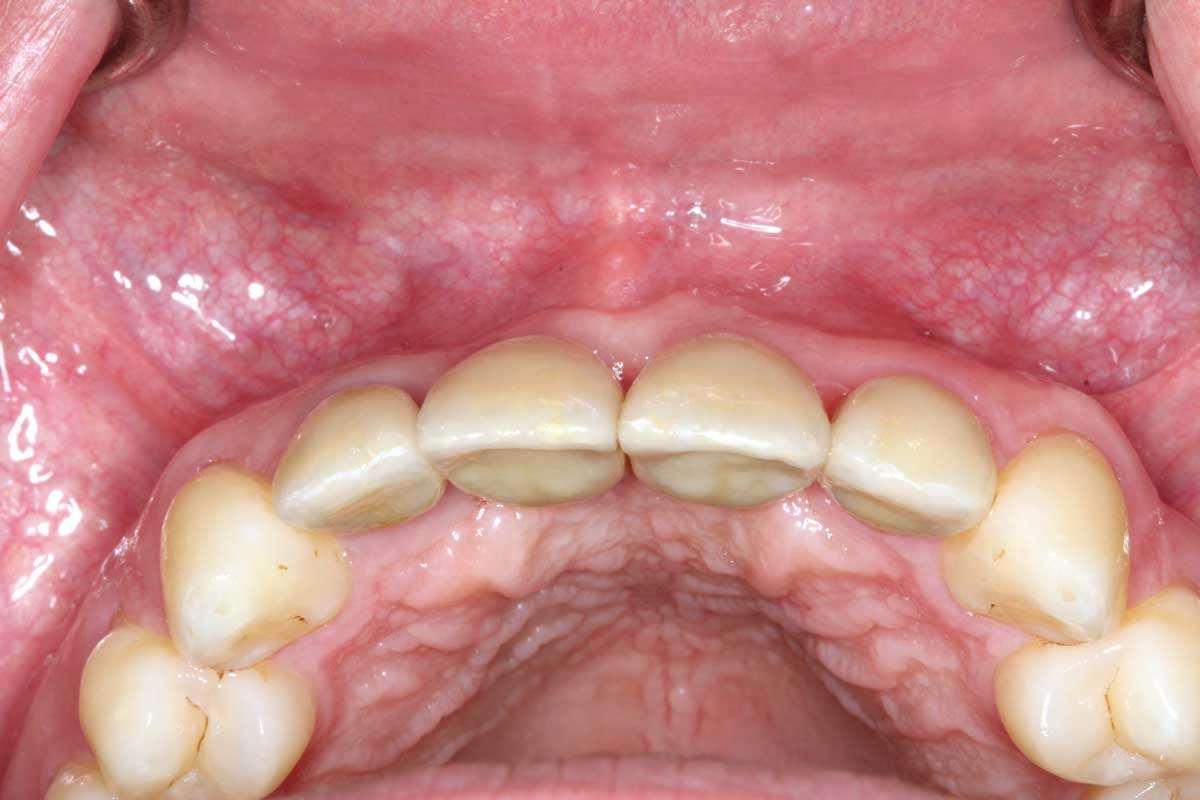

23/26 - Final clinical situation 12 months after augmentation

Ridge augmentation in the maxilla with maxgraft® bonebuilder in the aesthetic zone - Dr. M. Kristensen

24/26 - Final clinical situation 12 months after augmentation